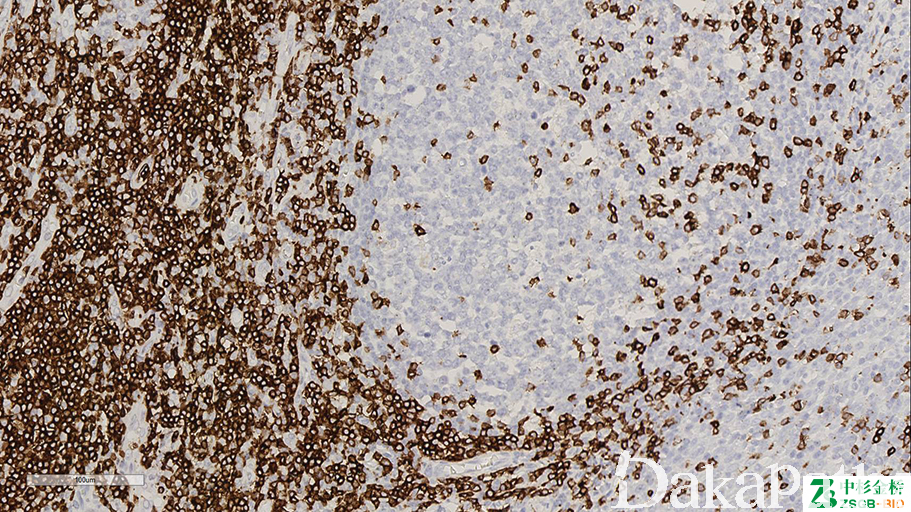

CD7

T 细胞表面抗原,免疫球蛋白超家族成员。表达于胸腺细胞膜表面最早的 T 细胞特异性抗原。

T 细胞淋巴瘤的诊断;

白血病免疫分型。

通常阳性(<95%,≥75%的病例阳性): 胆管癌、外周 T 细胞淋巴瘤、肠病相关 T 细胞淋巴瘤